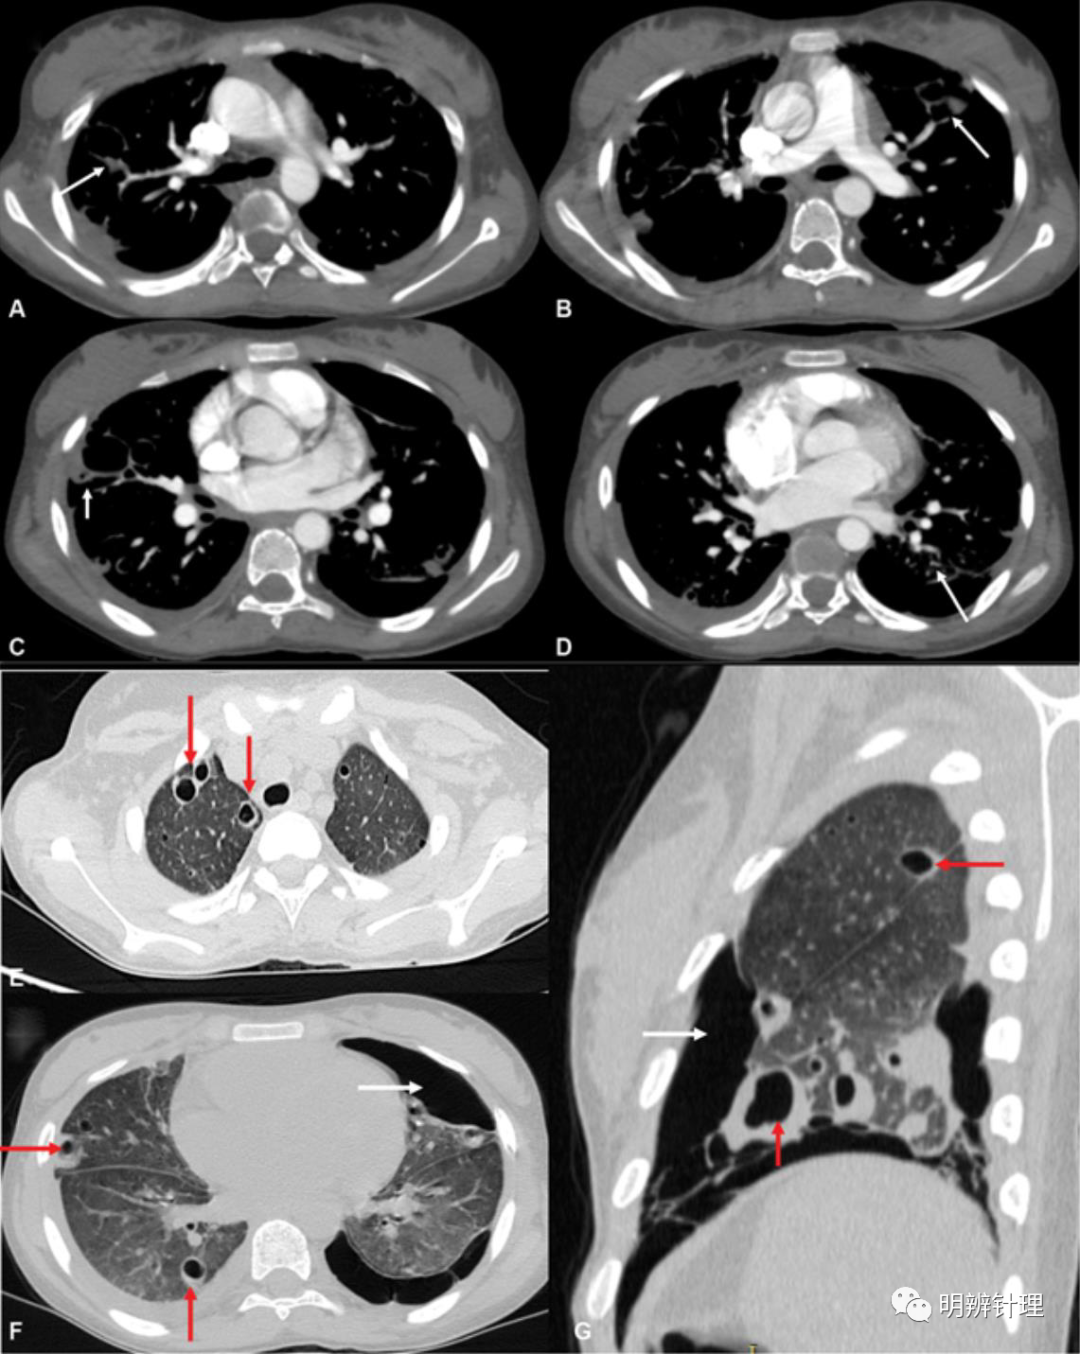

15 岁的女孩,咳嗽、发烧,伴呼吸急促和胸痛一周,因再生障碍性贫血接受免疫抑制治疗。CT显示多个结节性病变;CT 肺血管造影 (CTPA) 以排除肺循环中的脓毒性栓子。CTPA ( A–D ) 显示正常的肺血管系统,但有多个肺结节和供血血管(白色箭头)。肺窗 ( E–G ) 显示多发性气肿(红色箭头)和左侧气胸(白色箭头)。

诊断结果:痰培养:葡萄球菌